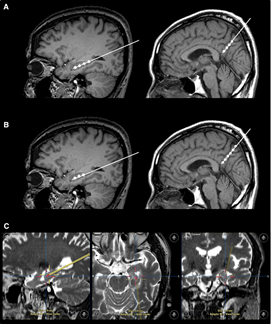

不僅如此,干細胞輸注治療安全可行。一項“立體定向腦內注射人間充質干細胞治療AD病人”的臨床試驗結果表明,在治療結束后的24個月隨訪時間內,患者沒有出現與干細胞治療相關的嚴重的不良反應。

2023年1月24日,國際學術期刊Movement Disorders (運動障礙)發表一篇研究性文章。研究者從胎兒中腦分離制備出多巴胺神經祖細胞,移植到患者的大腦中。設計方案:給15名患者(年齡<70歲)注射了三種劑量的細胞量(4×10*6,12×10*6,40×10*6細胞),隨后進行12個月的隨訪。研究結果顯示:低劑量組的運動能力恢復效果為11.6%,中劑量組為26%,高劑量組為40%。此外,沒有副作用,如出血、免疫排斥、炎癥和腫瘤形成。